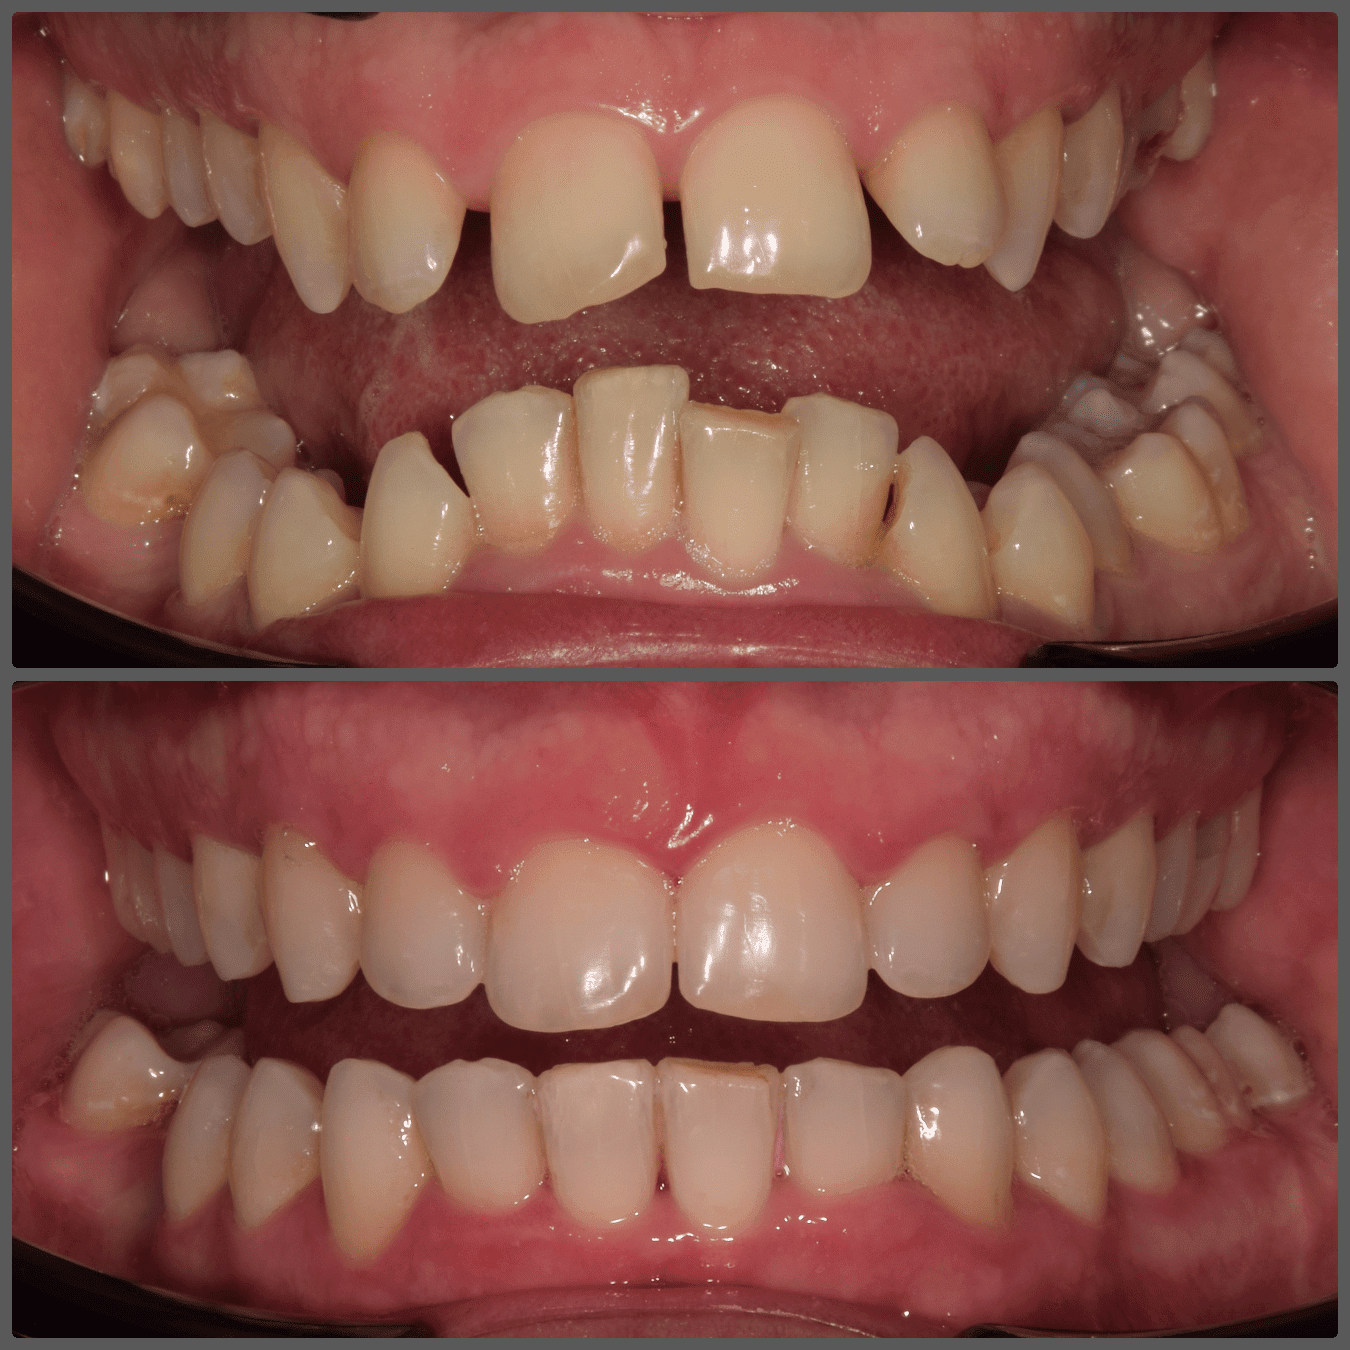

Bálint a 90 fokban elfordult jobb felső kismetszője miatt keresett meg engem. A vizsgálatokat követően kiderült, hogy a probléma ennél jóval komplexebb: súlyos keresztharapást, súlyos mélyharapást és felső rágósík billenést diagnosztizáltam nála. Alsó-felső H4 önligírozó fogszabályozó készülék, intermaxilláris gumihúzás és elülső harapásemelők segítségével korrigáltuk az eltéréseket. A bal oldali rágósík billenést fogszabályzási miniimplantátum alkalmazásával oldottuk meg. A bal felső-elülső fogakat felfelé mozgattuk, a miniimplantátumhoz húzva. Bálint esete igen komplex volt, ám kiváló együttműködésének köszönhetően 26 hónap alatt végeztünk a kezelésével (beleértve a 2-3 hónapos COVID-19 miatti leállást is). Az eredmény úgy gondolom magáért beszél!